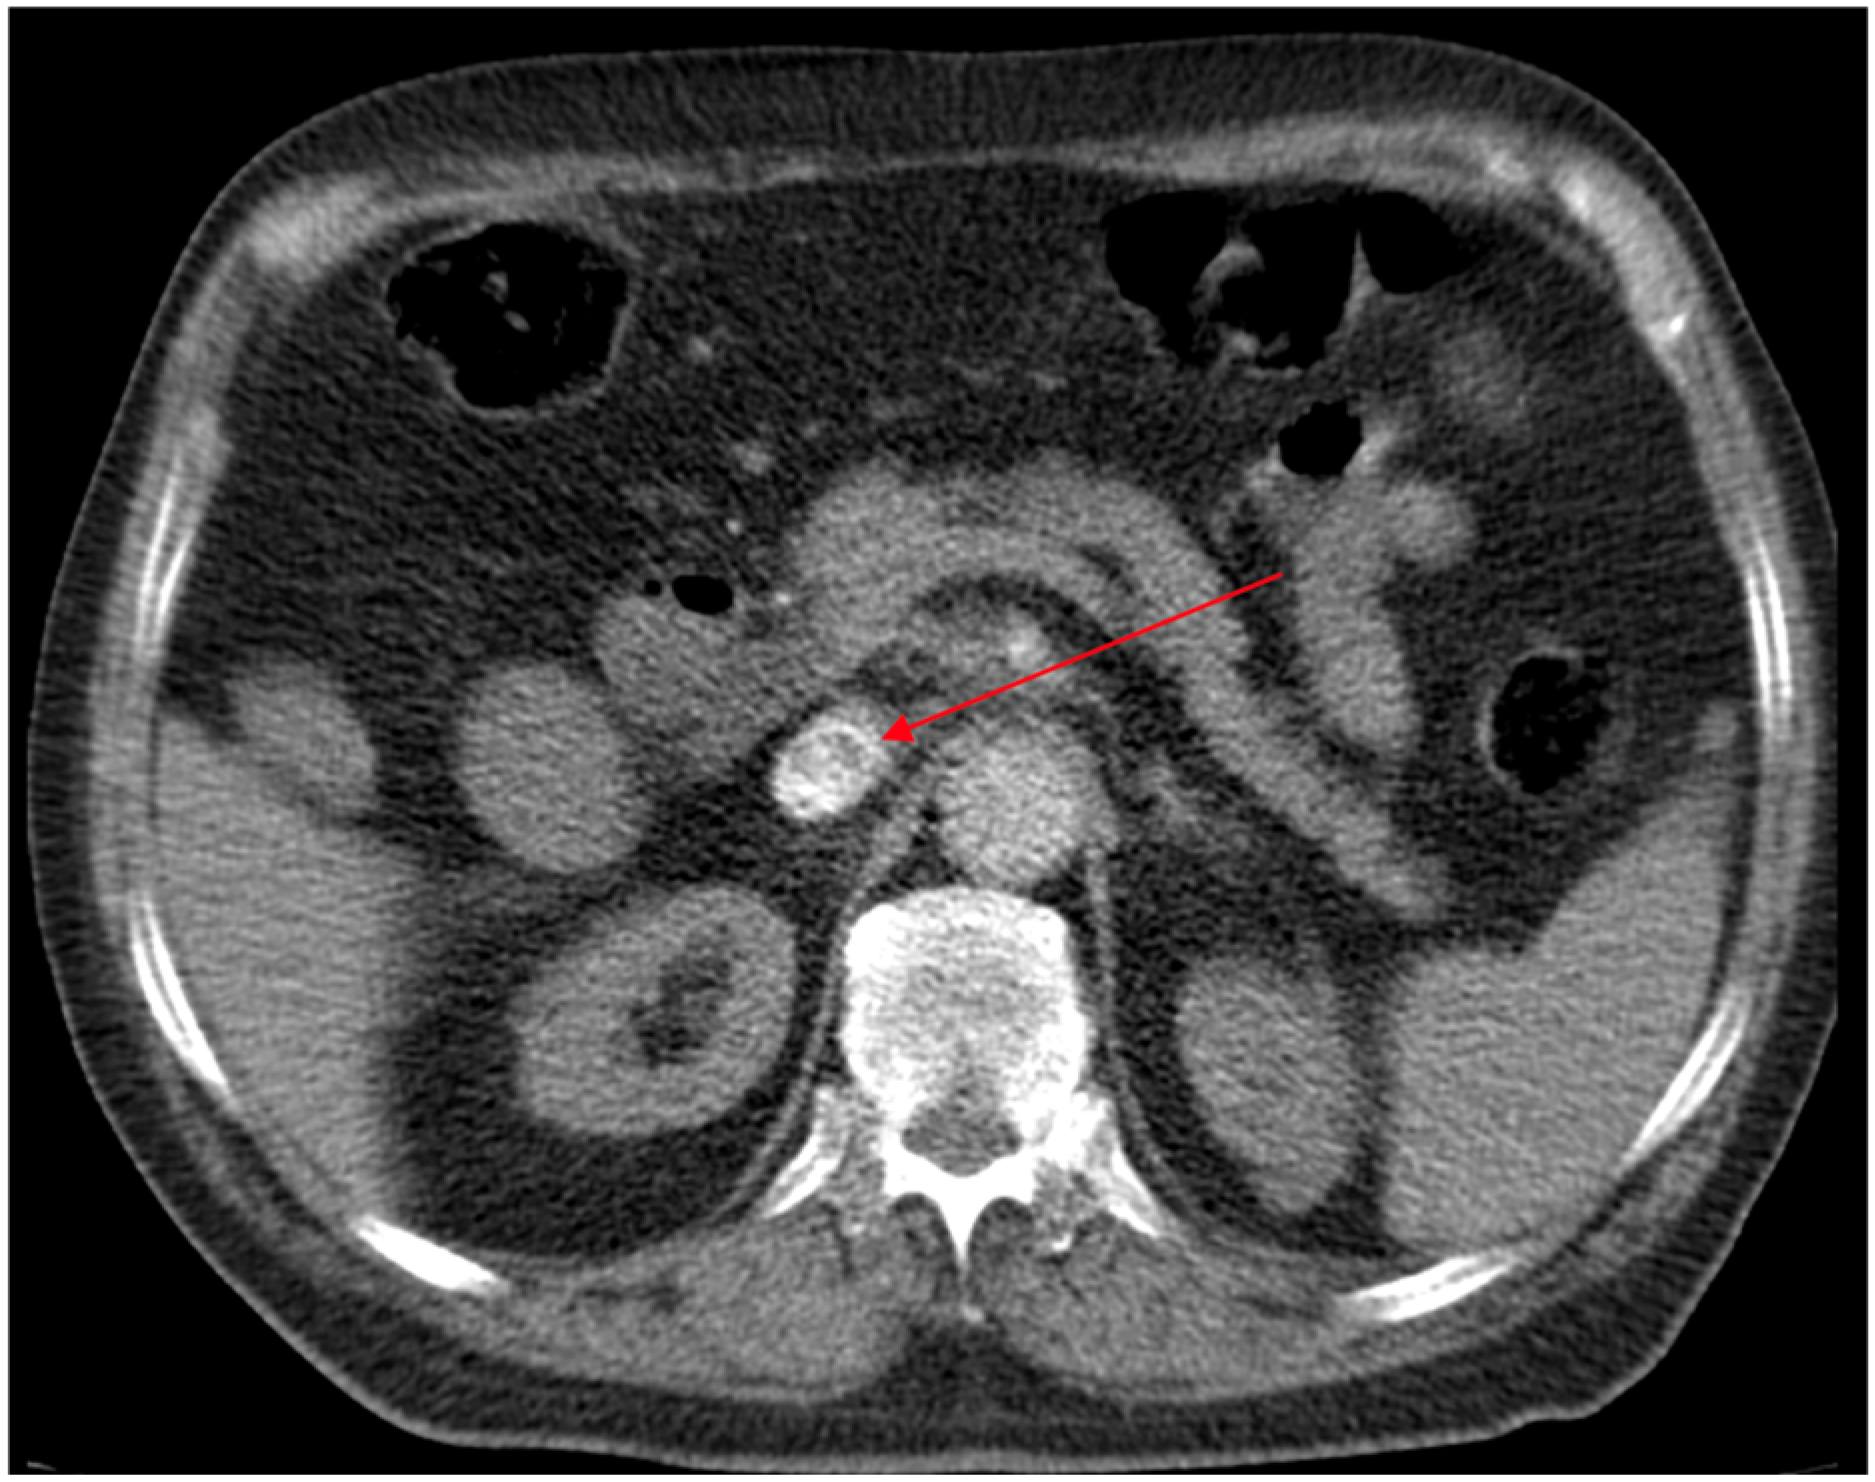

2.2.1. Past Medical History and Disease Course

2.2.2. Admission and Clinical Deterioration

2.2.3. Isolation of Acinetobacter baumannii and Eravacycline Therapy